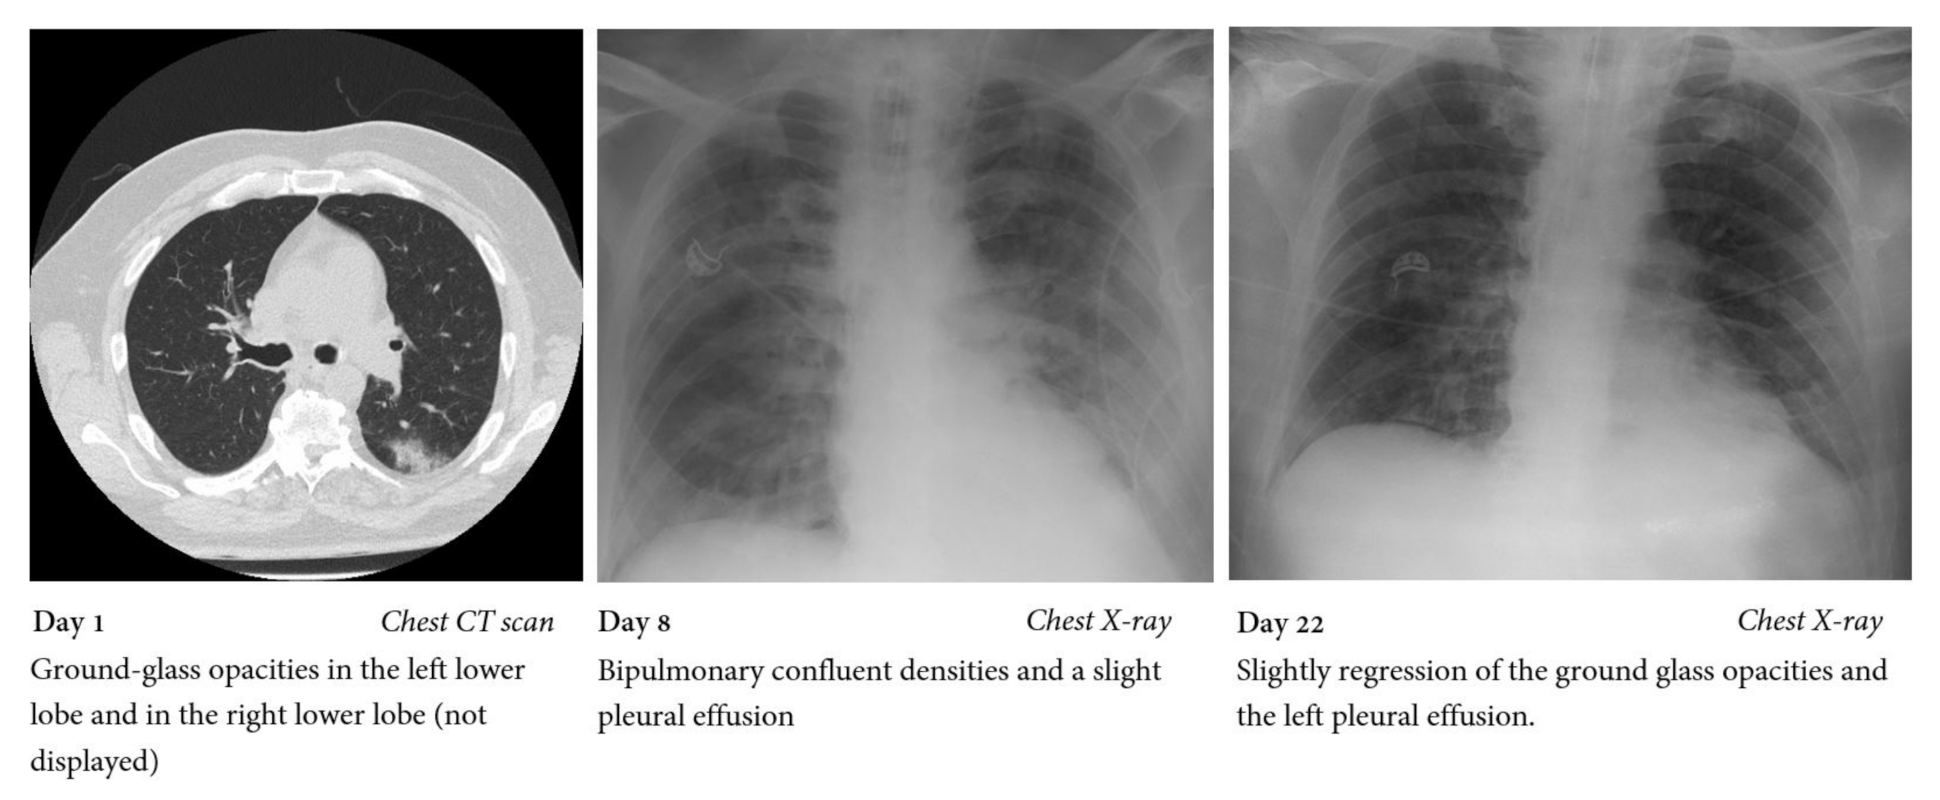

2. Case Report